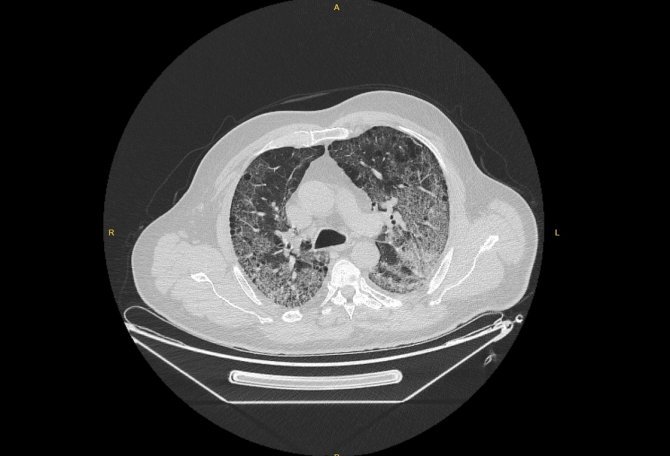

Anadolu Ajansı (AA) Ankara Şehir Hastanesinde Kovid-19 tedavisi gören hastalara ait akciğer görüntülerine ulaştı. Görüntülerde, hastalığın ne kadar hızlı ilerlediği ve akciğerleri nasıl tuttuğu ortaya çıktı.

Prof. Dr. Karalezli, koronavirüs tedavisi gören hastalara ait akciğer görüntülerinden hastalığın yol açtığı tahribatı ve hastalar üzerindeki etkileri anlattı.

Tedavisine rağmen nefes darlığı şikayetleri devam eden bir hastaya uygulanan akciğer görüntülemesinde hastanın her iki akciğerinin büyük bir bölümünü enfeksiyon kapladığını tespit ettiklerini ifade eden Karalezli, "Bu hastalığın sonunun ne olduğunu bilmiyoruz. Akciğer tutulumları, bu şekilde olduğu zaman hastaları oksijen tedavisi ile gönderiyoruz. Çok yeni bir hastalık olduğu için bu seyir nasıl olacak? Geriye dönüş var mı? Takiplerle öğrenebileceğimiz bir durum." dedi.

Normal akciğer görüntüleri ile koronavirüs hastalarının akciğer görüntüleri arasında ciddi farklar bulunduğunu belirten Karalezli, şu bilgileri verdi:

"İnsanların aradaki farkları anlamaları için her iki akciğer görüntülerine de yer verdim. Görüntülerdeki beyazlıklar akciğerdeki tutulumu gösteren görüntüler ne yazık ki. Bu hastalar yoğun bakım hastaları. Filmler birbirine az çok benzeyen şekilde. Altta yatan hastalığı olanlarda ise daha kötü seyrediyor."

Kliniğe yeni başvuran bir hastanın, 5 Ağustos'ta çekilen tomografi görüntülerindeki tipik koronavirüs görüntülerinin olduğunu ifade eden Karalezli, hastanın bir hafta içerisindeki tomografi görüntüsünde ciddi değişiklik olduğunu ve enfeksiyonun çok arttığını söyledi.